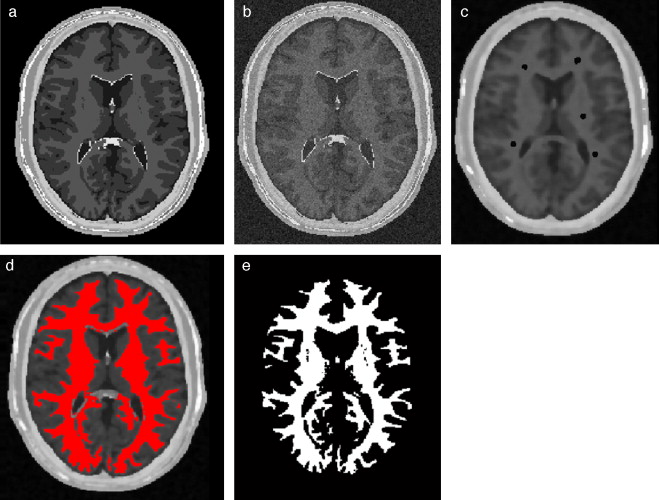

4.1. Caso 1: segmentación Region Growing - BrainWeb

Con el interés de segmentar la zona de la materia blanca, se utilizó el algoritmo de Region Growing en el phantom discreto completo original. La zona segmentada fue comparada con la zona de la materia blanca proporcionada por BrainWeb . Para este fin, se empleó el análisis de texturas con el cálculo de descriptores estadísticos en ambos volúmenes y los respectivos porcentajes de error entre ambos. En la figura 24 se presenta los resultados obtenidos al segmentar la zona de la materia blanca en el volumen phantom con dimensiones de 181 × 217 × 181 (X × Y × Z ), con voxels isotrópicos de 1,0 mm3 , por visualización se presenta el corte axial 98. En la figura 24 .a se presenta la imagen phantom original, mostrando el corte número 98 del phantom . En la figura 24 .b se presenta la zona segmentada empleando el algoritmo Region Growing con seis seed points (semillas) elegidos de manera arbitraria sobre el área de la materia blanca, en forma de esferas volumétricas de 2 mm de radio, con el centro en las coordenadas X,Y,Z : Seed1= (66,59,98), Seed2 =(67,101,98), Seed3 =(60,158,98), Seed4 =(112,55,98), Seed5 =(113,103,98) y Seed6= (127,149,58). En la figura 24 .c se presenta la zona de la materia blanca proporcionada por BrainWeb.

|

|

|

Figura 24. Materia blanca segmentada en volumen phantom . (a) Corte axial número 98 de la imagen de phantom original. (b) Materia blanca segmentada con metodología propuesta empleando algoritmo Region Growing. (c) Zona de la materia blanca segmentada por BrainWeb . |

En la tabla 1 se presentan los valores estadísticos y los respectivos porcentajes de error, donde se puede observar que el porcentaje de error de las zonas segmentadas por Region Growing y la zona de la materia blanca proporcionada por BrainWeb no supera el 0,2487% para el caso del número global de pixels y el 0,2909% para los descriptores estadísticos.

| Nro. pixels | Media | Desviación estándar | Asimetría | Homogeneidad | Entropía | |

|---|---|---|---|---|---|---|

| Region Growing | 682.820 | 0,0947 | 0,2928 | 2,7687 | 8,6655 | 0,4519 |

| Phantom BrainWeb | 674.777 | 0,0949 | 0,2931 | 2,7641 | 8,6404 | 0,4527 |

| %error RegionGrowing-phantom | 0,2487 | 0,2407 | 0,1078 | 0,1644 | 0,2909 | 0,1643 |